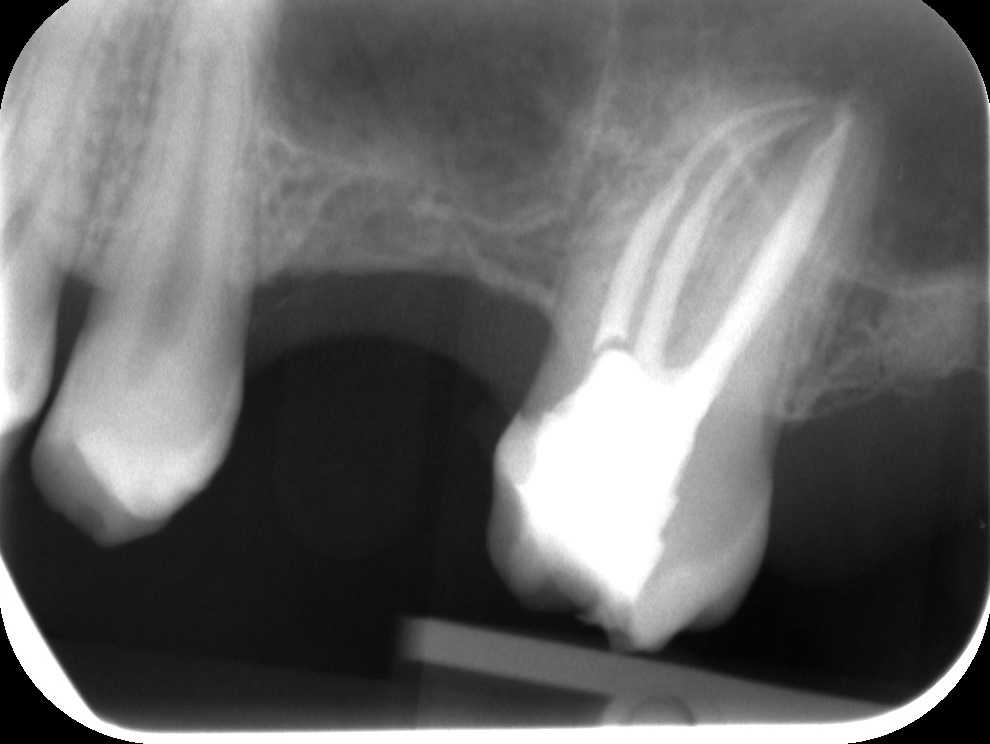

A második ülésben a fogból eltávolítjuk az ideiglenes lezárást, majd egy újabb fertőtlenítés következik, és a tisztítás után elvégezzük a gyökértömést. A kontroll röntgenfelvételen jól kivehető, hogy a fognak elöl nem egy, hanem két gyökere van: ha ezt nem sikerül megtalálnunk és letömnünk, az később panaszokat és gócos tüneteket okozhat. A mikroszkópos berendezés nagy segítséget nyújt az ehhez hasonló extra foggyökerek felderítésében. Most is így történt, és az érintett fog megmenekült attól, hogy el kelljen távolítani a folyamatosan fennálló panaszok miatt.